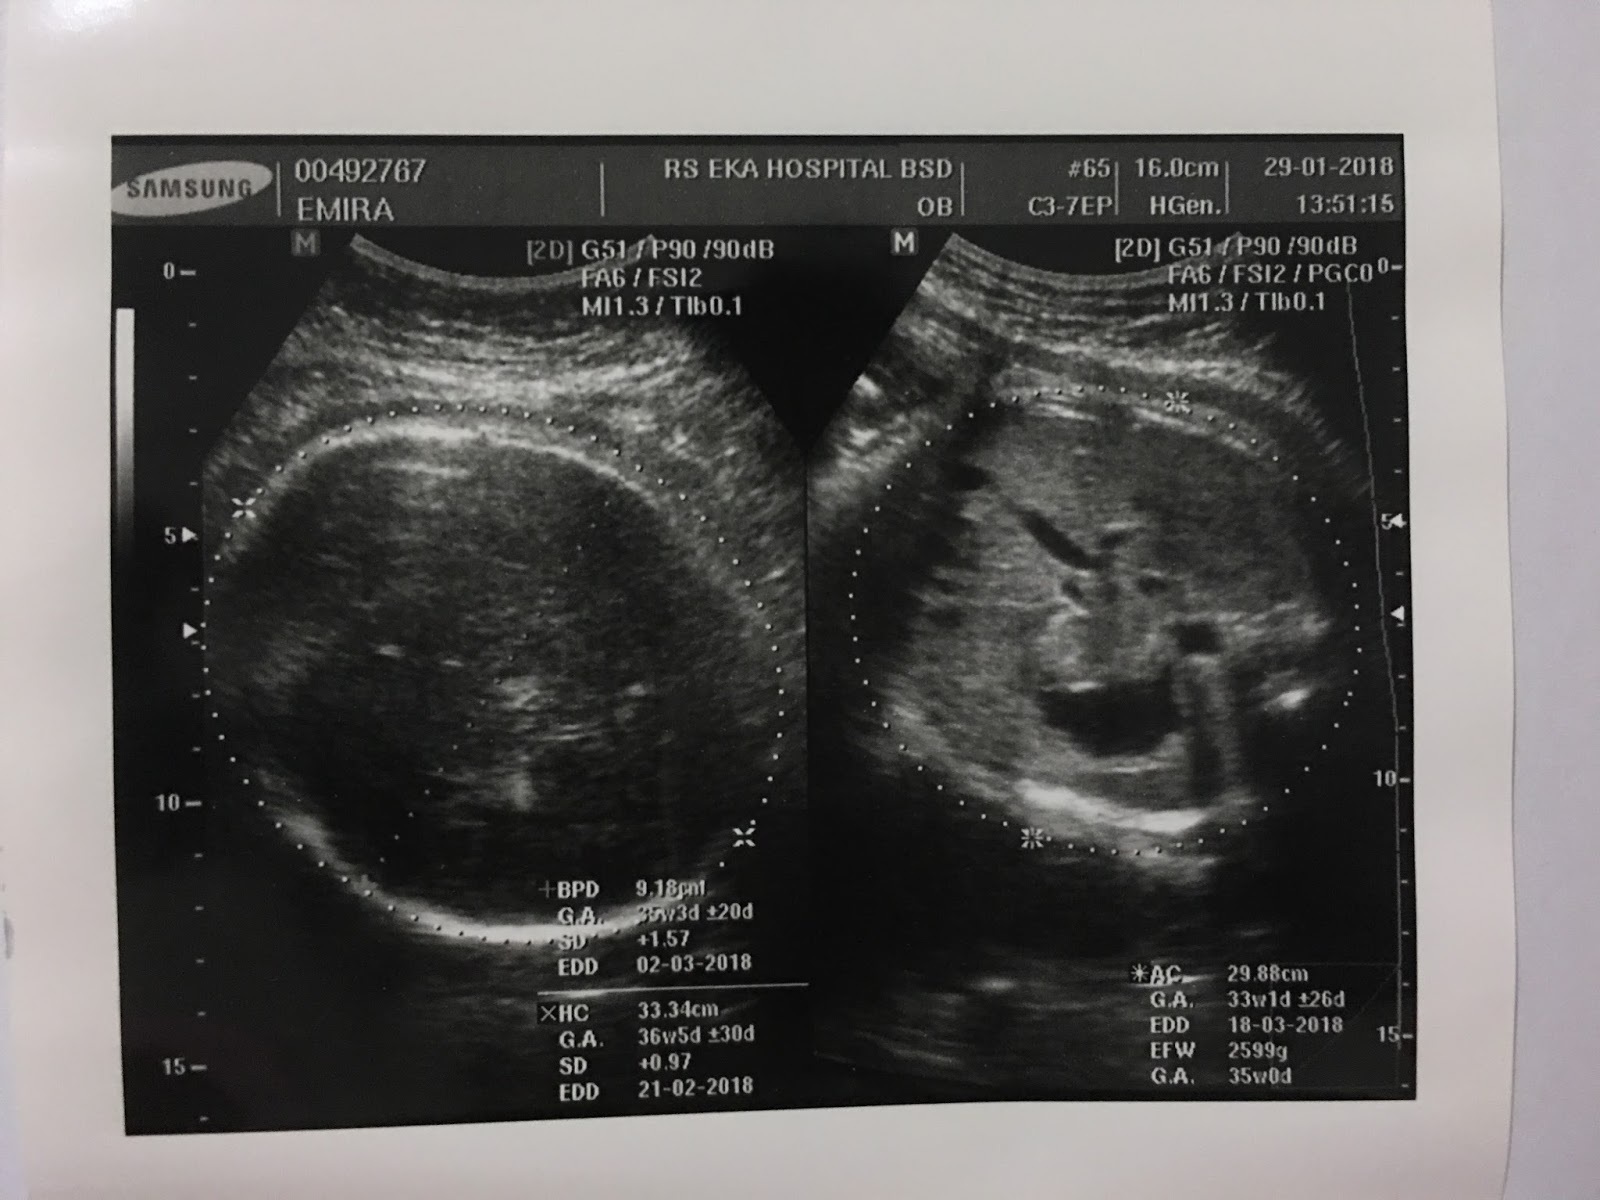

hasil usg 35 minggu - IbuHamil.com

hasil usg 35 minggu - IbuHamil.com

Story of My Journey: USG Kehamilan 35 Minggu

Story of My Journey: USG Kehamilan 35 Minggu